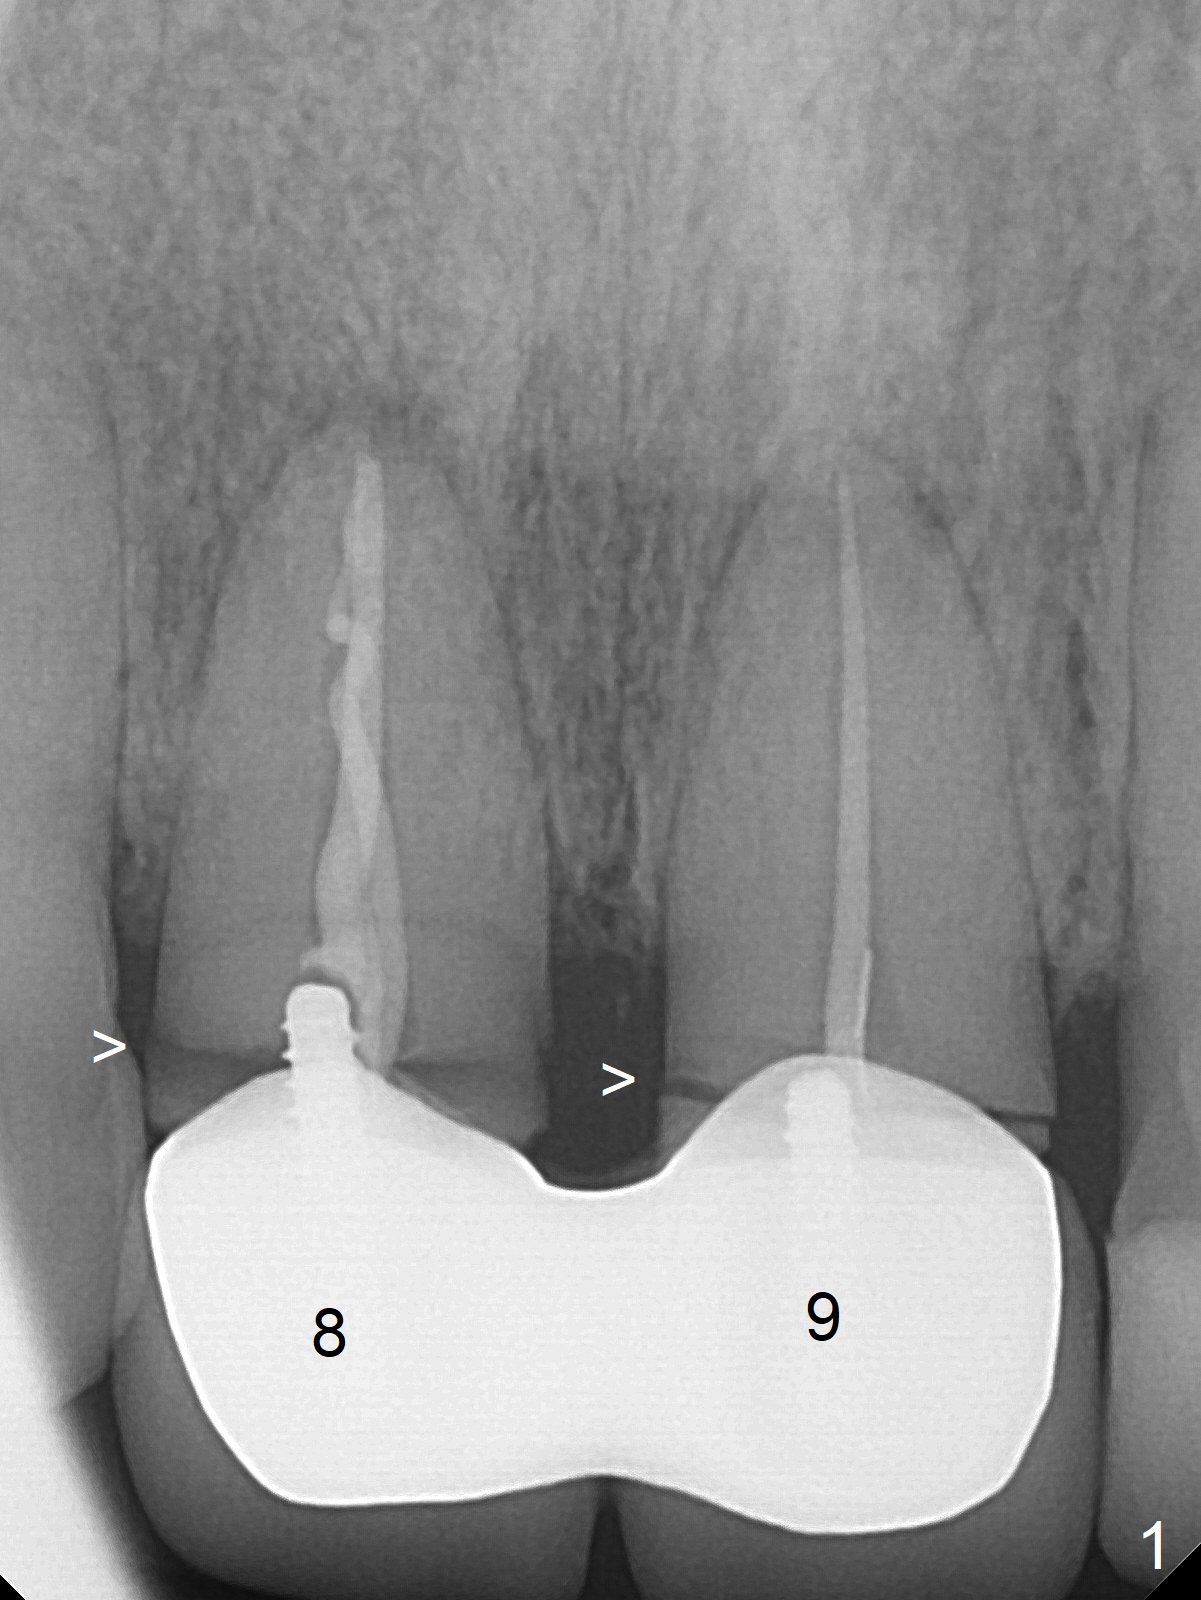

A 36-year-old woman fractures the teeth 8 and 9 while the implant at #3 is healing (Fig.1 arrowheads). It appears that the teeth are wide enough to accept 4.5x14 mm implants (Fig.2).